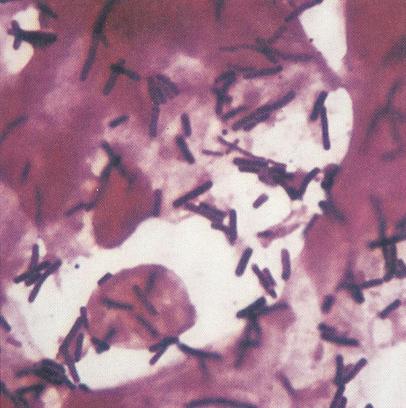

In conditii normale, pe frotiul colorat Gram se observa bacili Gram pozitivi, drepti sau usor incurbati cu laturile paralele, cu grosimea si lungimea variabile pana la polimorfism, uneori filamentosi, care reprezinta flora lactobacilara (bacili Döderlein, vezi figura 21.5.5.1)2. In vaginoze, flora lactobacilara este inlocuita cu bacili Gram variabili (G. vaginalis, Bacteroides spp.) si bacili Gram negativi incurbati (Mobiluncus) – vezi figura 21.5.5.2. Vaginoza se caracterizeaza prin prezenta de “clue cells” – celule vaginale superficiale ce prezinta pe suprafata lor abundenta flora bacteriana (vezi figura 21.5.5.3). Prezenta formatiunilor rotund-ovalare Gram pozitive este sugestiva pentru candidoza vaginala (vezi figura 21.5.5.41;2.

Fig. 21.5.5.3: Frotiu sugestiv pentru vaginoza bacteriana: (coloratie Gram, x1000, imagine din colectia proprie a laboratorului)